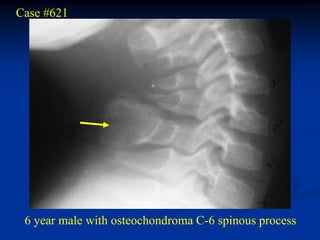

Case #621

6 year male with osteochondroma C-6 spinous process

CT scan